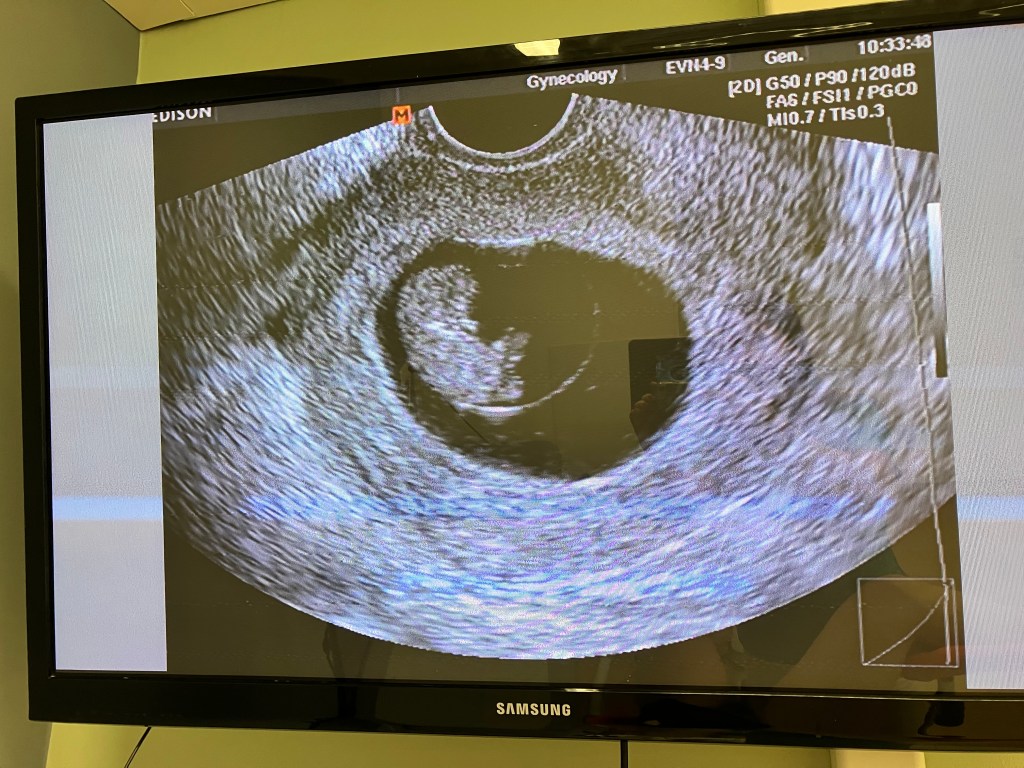

More importantly, there’s a two-legged family member joining us in July! Claire is pregnant! And it’s another boy! Once again, this an amazing surprise since we were told some years ago we would never have biological children.

Pray for Claire’s health. She’s managing it very well, but we were informed that she has minor gestational diabetes. While a challenge, it’s great to have an explanation for why this pregnancy has been much harder than previous ones, and to be able to do something about it.